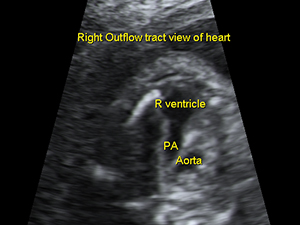

The pulmonary outflow tract from the fetal heart